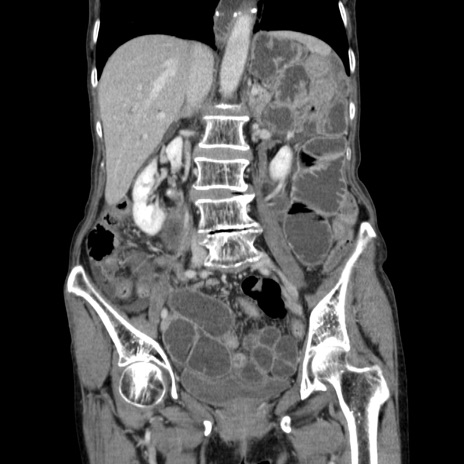

症例25(冠状断像)

【症例】80歳代女性

【主訴】胸のつかえ感

【現病歴】約9時間前に食後から胸のつかえた感じあり、嘔吐あり、来院。

【既往歴】胃癌(全摘)、胆摘、虫垂炎

【身体所見】心窩部に圧痛あり、反跳痛なし。

【データ】WBC 5700、CRP 0.05